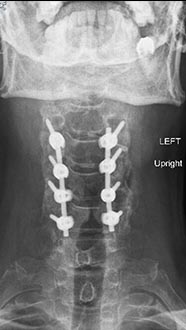

56 year old woman who presented with severe neck pain with numbness of both hands and balance problems due to severe cervical stenosis. Patient underwent C4 to C7 anterior cervical discectomy and fusion with complete resolution of her neurological symptoms.